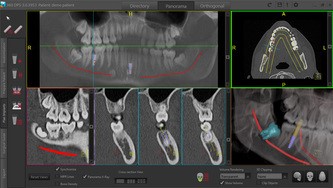

Using 3D CBCT scan data we can help you diagnose, plan, and perform dental implant rehabilitations with increased predictability, patient comfort and superior esthetic results.Please contact us for scan protocols to insure accurate information is obtained. For denture patients there are SureMark CT-Scan Markers that need to be placed before scanning.

360Guide helps you to predictably transfer your treatment plan into clinical reality. Complete information about the quality and quantity of the bone makes it possible for you to determine the ideal location for your patient’s implants. This will increase the probability for a successful operation. Knowledge of the exact location of important anatomy, such as the mandibular nerve and the maxillary sinus cavities, provide confidence that implant placement will proceed smoothly and safely. Surgical guides help ensure that all of your patient’s implants are properly placed using all of this valuable information.